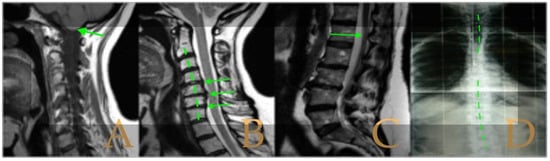

The MRI showed (Figure 8): descent of the cerebellar tonsils and increase of the supracerebellar space, straightening of the cervical spine, multiple protrusions, and discrete central spinal cord oedema C5-C7, mild scoliosis in the thoracic spine, and somewhat tense aspect of the spinal cord. The conus medullaris was at the level of the lower third of the L2 vertebra. Disc disease L5-S1. Tarlov cyst at S2. On the full-spine X-rays, there was dysmetria of the lower extremities with shortening of the left lower extremity estimated to be 1 mm at the level of the acetabular roofs and 6 mm at the level of the iliac crests. Levoconvex lumbar scoliosis was estimated at 5°, and levoconvex cervicothoracic scoliosis was estimated at 3° (both total, including all vertebrae). The estimated lateral curvatures, including all vertebral bodies in each region, were cervical lordosis 4°, thoracic kyphosis 32°, and lumbar lordosis 40°.

The MRI showed (Figure 9): descent of the cerebellar tonsils, ischemic foci in the white matter of the cerebral hemispheres, and oedema in the optic nerve sheaths. Kyphosis of the cervical spine (especially C5-C6-C7). Tense aspect of the cervical spinal cord. Disc disease: C3-C4-C5-C6-C7-T1. Ischemia and cervical and thoracic oedema. Straightening and scoliosis of the thoracic spine. Lumbar lordosis straightening. Conus medullaris at the level of the middle third of L1. Postsurgical changes in L4-L5 (disc prosthesis). The full-spine X-rays showed cervical, thoracic, and lumbar scoliosis, with the biggest curve being dextroconvex of wide radius in the thoracic and lumbar region.

Figure 8. Imaging of patient 8. A: MRI of the posterior fossa with descent of the cerebellar tonsils (arrow) below McRae line (green line); B: cervical MRI with straightening of the cervical spine (interrupted line) and C5-6-7 disc disease (stars); and C: conus medullaris at the level of the lower third of L2 (arrow) and L5S1 disc disease (star).

Figure 9. Imaging of patient 9. A: MRI of the posterior fossa, descent of the cerebellar tonsils (arrow), and increased supracerebellar space (star); B: straightening of the cervical spine (interrupted line) and suboccipital craniectomy with C1 laminectomy (star); and C: conus medullaris at the level of the middle third of L1 (arrow) and L4L5 disc prosthesis (star).